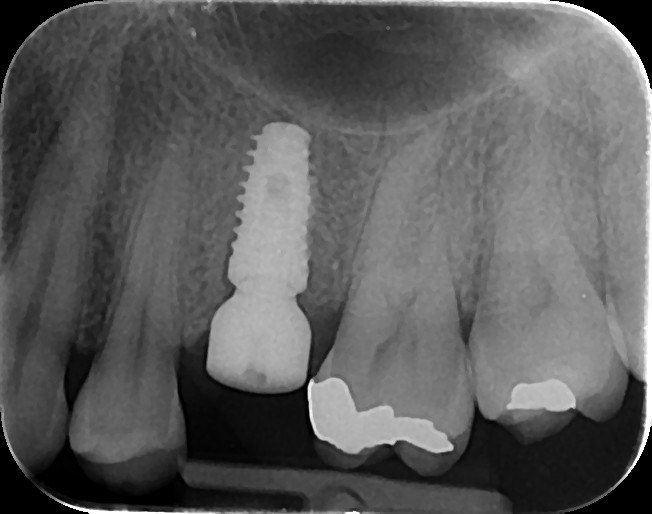

4. What option can be selected regarding the implant seen in this X ray?